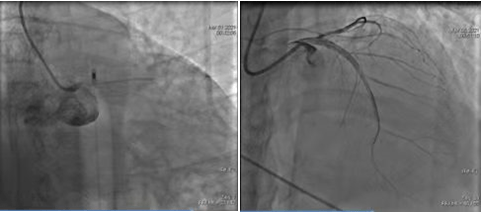

術(shù)前CAG示:LCX中段80%狹窄 ;OCT示纖維斑塊,最小管腔面積3.1mm2

術(shù)后OCT示:支架貼壁及膨脹良好,無夾層及血腫